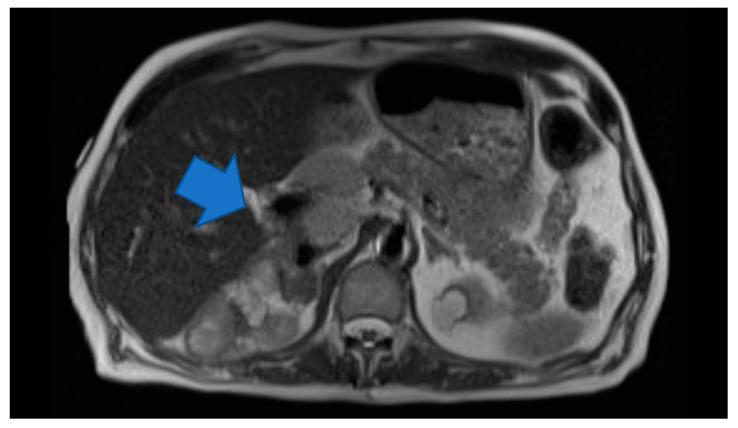

老年患者复发性嗜铬细胞瘤。

Recurrent Pheochromocytoma in an Elderly Patient.

嗜铬细胞瘤是一种罕见的神经内分泌肿瘤,可发生于所有年龄段人群,常见于 40 至 50 岁。家族性嗜铬细胞瘤的诊断年龄大多在 20 至 30 岁。嗜铬细胞瘤可为良性或转移性,常表现为孤立性肿瘤或伴有其他神经内分泌综合征。我们报告了 1 例 60 岁老年男性,因嗜铬细胞瘤行腹腔镜肾上腺切除术,但 10 年后发生转移性嗜铬细胞瘤复发。我们还进行了文献复习,以了解该肿瘤的流行病学和表现,并强调应保持警惕,及时诊断和治疗复发性嗜铬细胞瘤。